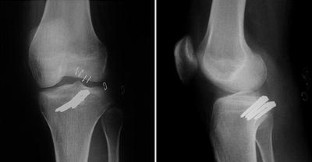

This study reports a case of unusual vascular complication related to the staple fixation for the tibial avulsion fracture of the posterior cruciate ligament (PCL). The patient, who experienced recurrent hemarthrosis 12 months after staple fixation for the avulsion fracture of the PCL, was successfully managed by removing the staple and suturing the bleeding focus of the popliteal artery. Injury to the popliteal artery by the prominent staples could be the culprit causing the recurrent hemarthrosis. This type of delayed popliteal artery injury should be kept in mind in open reduction and internal fixation for the tibial avulsion fracture of the PCL.

Fig. 4